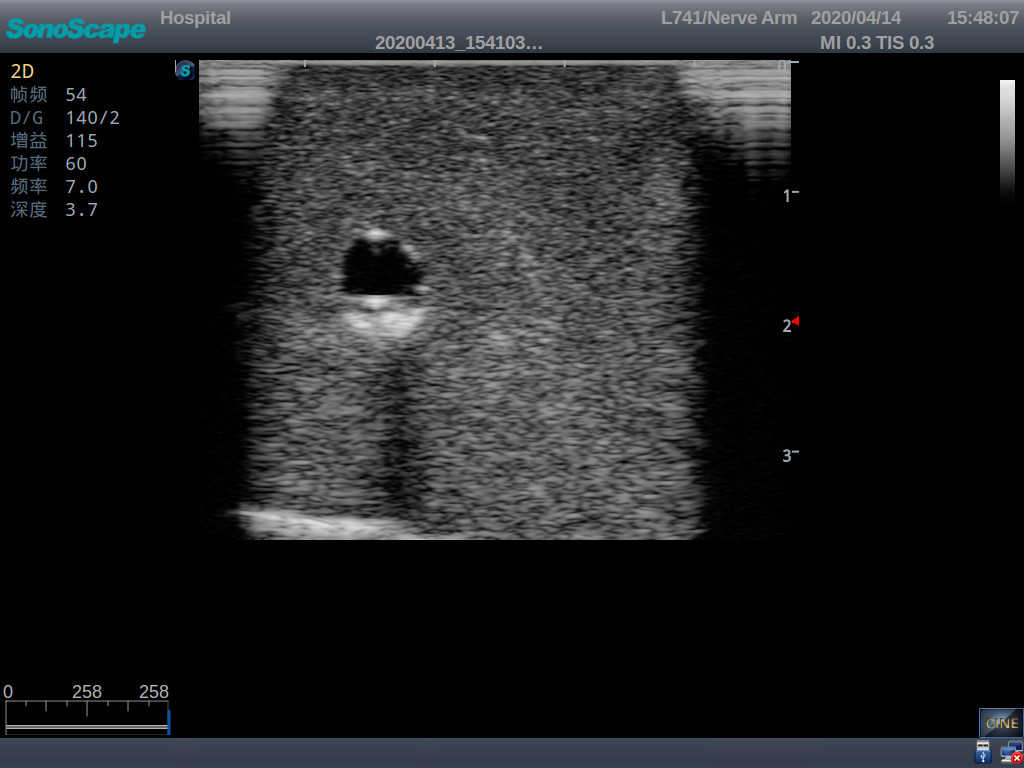

Model TYE1510.1

It is a model covering up from lobulus auriculae plane to the umbilical plane, and it has anatomical structures like clavicle, rib, sternocleidomastoid, jugular vein and basilic vein.

1)   Made of high molecular polymer ultrasound material, close to the real skin

2)   It can be used by real ultrasound machines

3)   Clear and real images of the tissues and organs (basilic vein and superior vena cava)